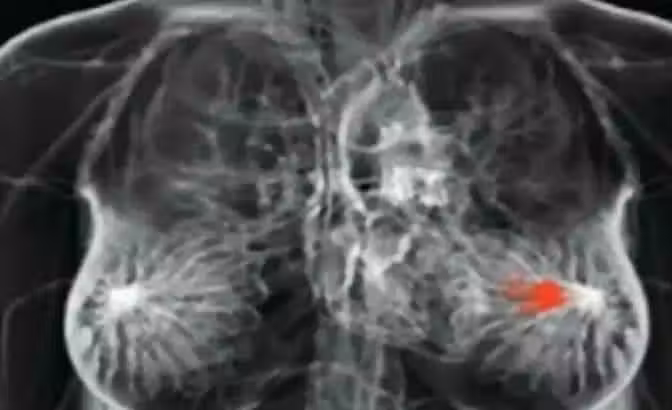

身體發生「4狀況」是「乳癌」前兆!別再只靠手摸「胸部腫塊」測腫瘤 女性朋友一定要知道

乳房異常疼痛

如果你還認為在乳房中發現了一個局部疼痛的獨立腫塊,就是乳房發生癌症的跡象的話,那你可能就錯了!事實上,乳癌出現的腫塊其實都是分散在乳房的各處,像是種子一般的,甚至在某些情況很多乳癌患者是根本沒有腫塊的。